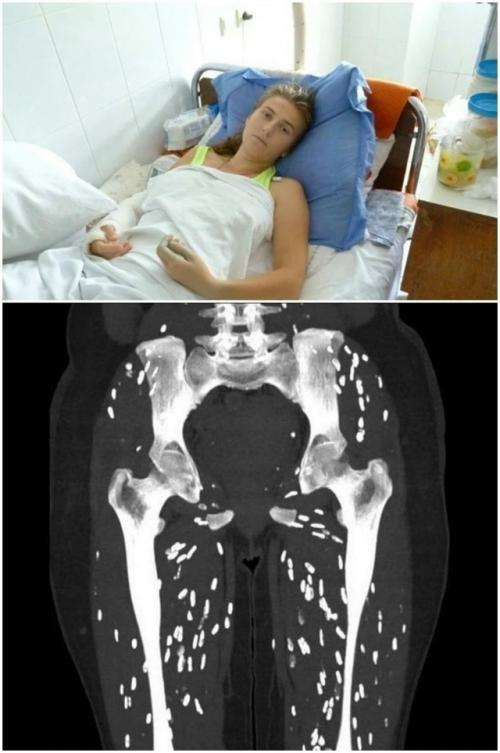

Почему слезает кожа на пальцах, стопах? Виной этому инфекция грибковой природы. Наличие грибковой инфекции – худшая причина. Симптоматика связана не только с тем, что кожа облезает, о наличии недуга свидетельствуют и другие отклонения:

- появляется неприятный запах;

- ногтевая пластина на пальцах ног у ребенка или взрослого меняет свой цвет;

- ногти становятся ломкими;

- возникает зуд.

При повышенной степени потливости ступни на ногах выступают в роли самой подходящей поверхности, на которой быстрыми темпами растут и размножаются патогенные микроорганизмы. Если слишком кутать ножки ребенка или во взрослом возрасте надевать достаточно тесную или закрытую обувь в разгар лета, то создаются самые подходящие условия для появления идеальной грибковой среды (чрезмерное тепло, недостаточное количество света, появление влаги).

Пациенты, которые заметили первую симптоматику грибковой инфекции, должны безотлагательно обратиться в медицинское учреждение за квалифицированной помощью. Чем дольше оттягивать такой поход, тем болезнь становится запущенней (самостоятельно она не проходит). Лечить ее будет сложней, для полного устранения недуга понадобится длительный терапевтический курс.